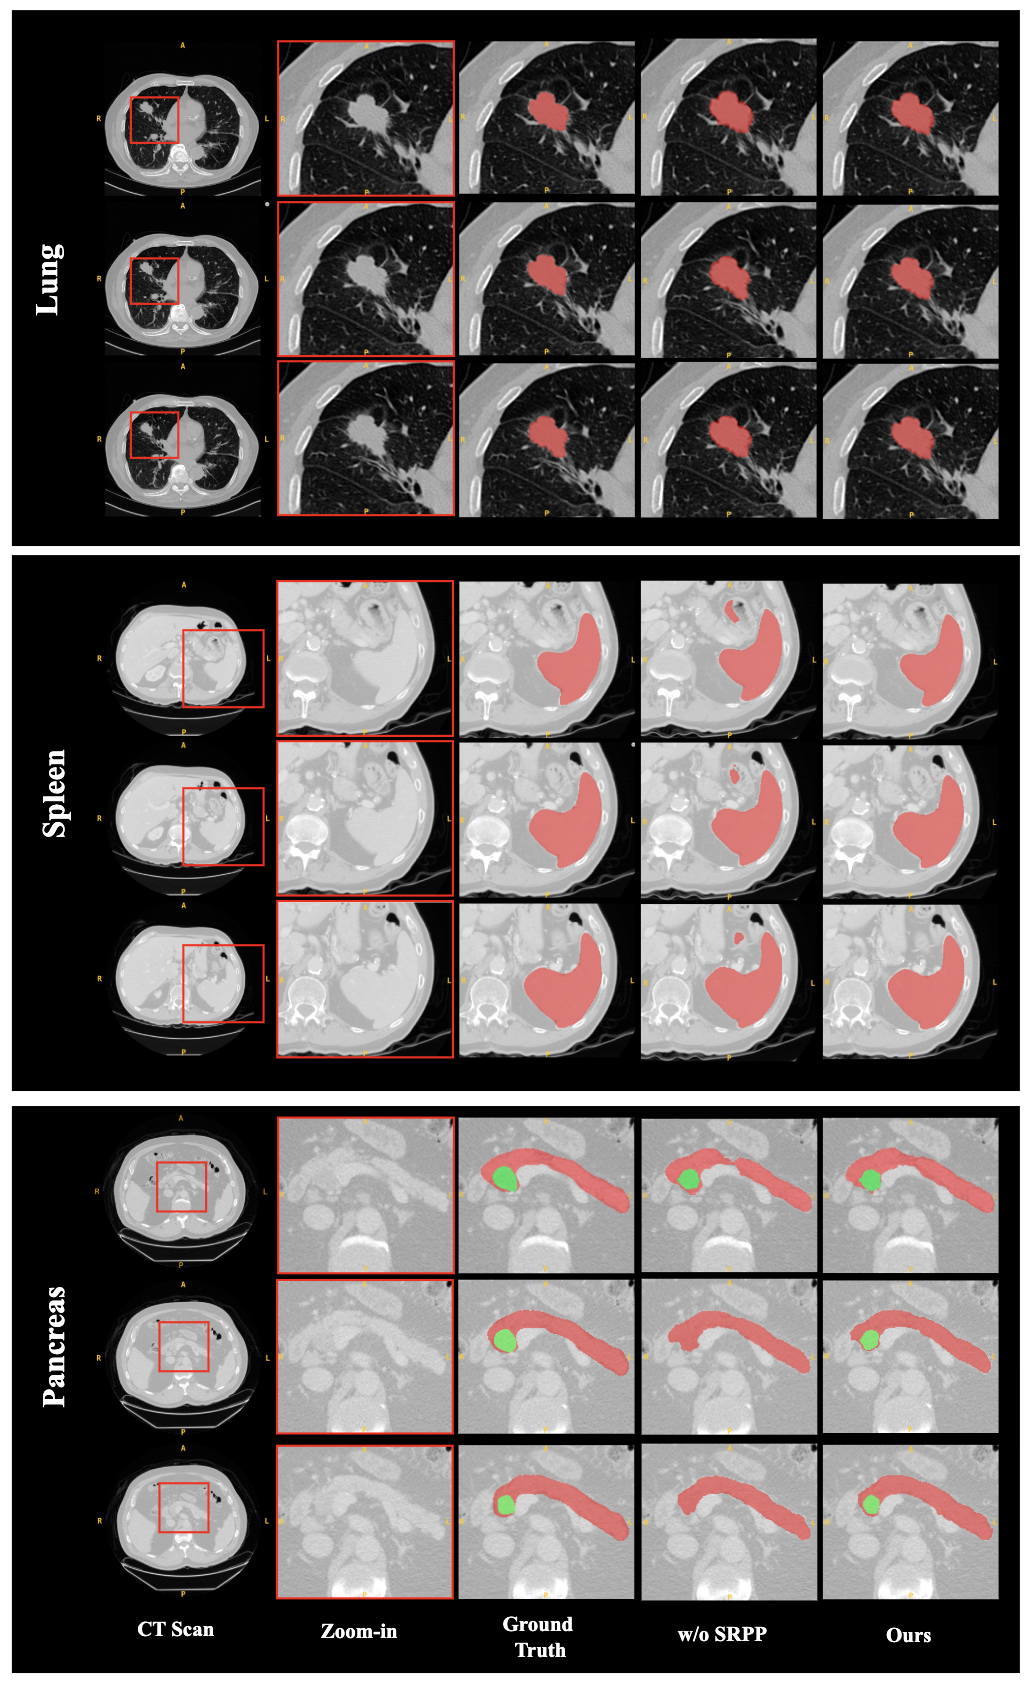

D.2 Effectiveness of SRPP Module

To validate the effectiveness of our proposed SRPP module, we compared our full model against an architectural variant where the SRPP module was removed (“w/o SRPP”). The quantitative results of this comparison are presented in Table 4.

The results demonstrate the effectiveness of the SRPP module in enhancing segmentation performance. Across all three datasets, the inclusion of SRPP brings consistent improvements. The impact is particularly pronounced on the more challenging datasets and in boundary-sensitive metrics. For instance, on the Pancreas dataset, integrating the SRPP module boosts the Dice score from 0.6459 to 0.7039 and significantly reduces the HD95 from 21.9181 to 14.9232. A similar substantial improvement in boundary delineation is observed for Lung, where the HD95 metric drops dramatically from 8.5837 to 3.5148.

This substantial improvement highlights the SRPP module’s crucial role in capturing multi-scale contextual information. The visualization results in Fig. 5 further corroborate these findings.

Refer to caption

Figure 5: Visual comparison of segmentation results with and without SRPP module.